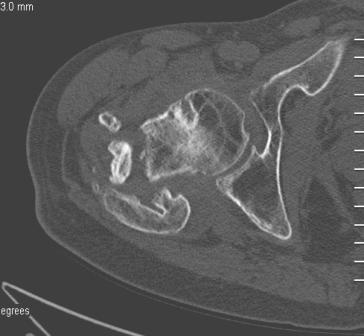

[Ortho] Сросшийся со смещением чрез-подвертельный перелом

Больной Н. 44 года травма 1,5 года назад июнь 2008 года чрез-под вертельный  перелом правого бедра. Во время лечения у больного развился алк делирий,  проводилось консертативное лечение перелома.

На КТ перелом сросся за счет костной мозоли.